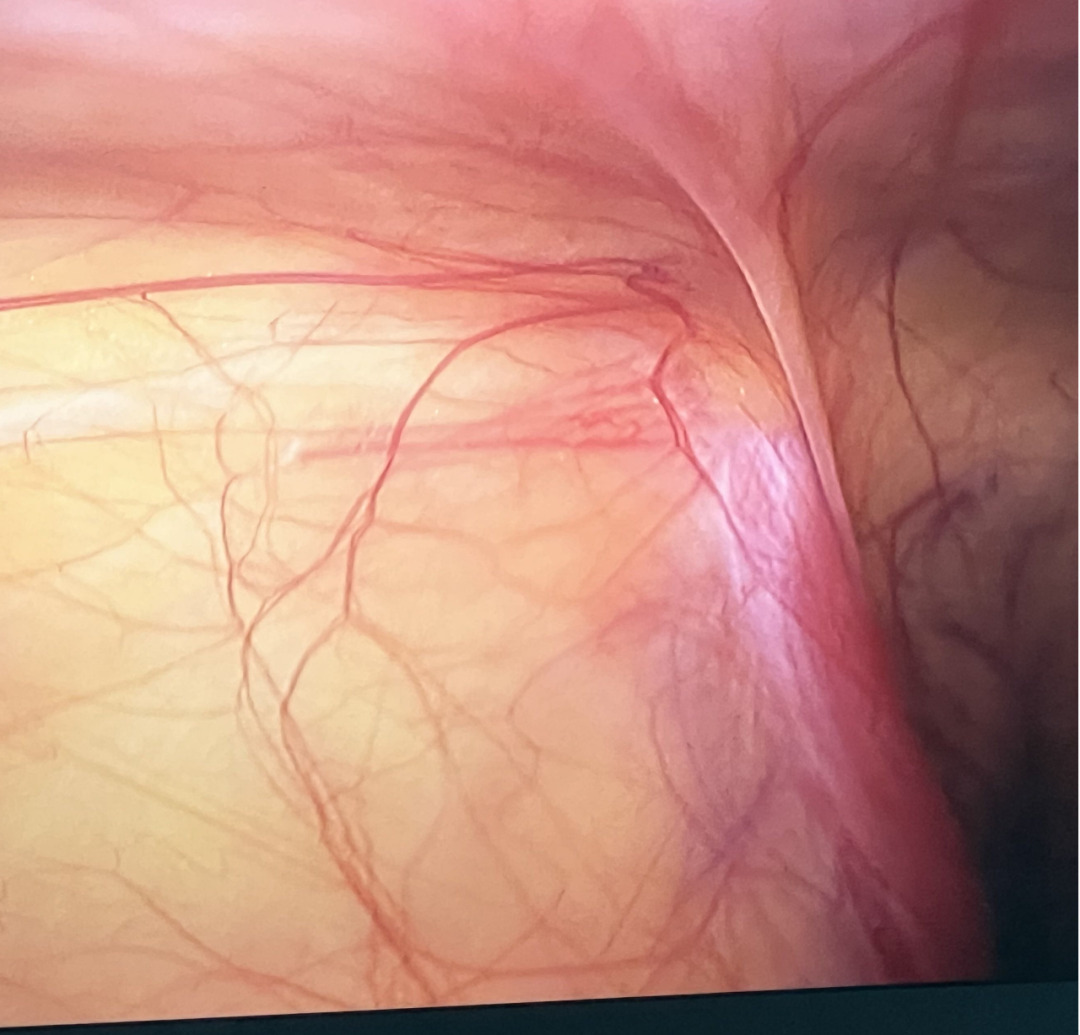

患儿转运至病房途中,张璇、余泽泓两名护士已提前备好抢救器械,不等住院手续办完,便同步开展胃肠减压、静脉穿刺扩容补液、抽血送检等操作,争分夺秒稳定患儿生命体征。与此同时,梁鸿熙、梁颖医师全程陪同患儿完成术前超声检查,精准明确“右侧腹股沟斜疝嵌顿,部分小肠淤血发黑”的诊断;汪登亮主治医师一边协调手术室开通“儿童急诊手术绿色通道”,一边耐心向家属讲解病情、术中风险及治疗方案,缓解家属焦虑情绪。

从患儿入院到进入手术室,术前准备高效完成,仅用时30分钟。。术中,汪登亮主治医师与梁鸿熙医师密切配合,精准复位嵌顿肠管、修复疝囊,仅15分钟便顺利完成手术。